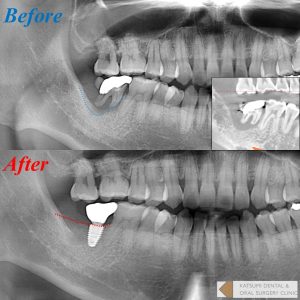

写真に示す症例では、歯周炎によって広範に骨吸収をきたし、通常の抜歯ではおそらくインプラント埋入自体が極めて困難になった可能性がありますが、本術式を選択することによってしっかり骨が回復している様子が分かると思います。本症例で使用した骨補填材リフィット®は材料の性質上レントゲン像はやや透過性を示しますが、骨質的には良好ですのでご安心ください。1年程度で骨様の所見となります。